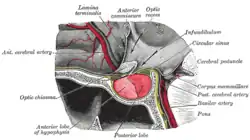

Anatomy - Biological engineering